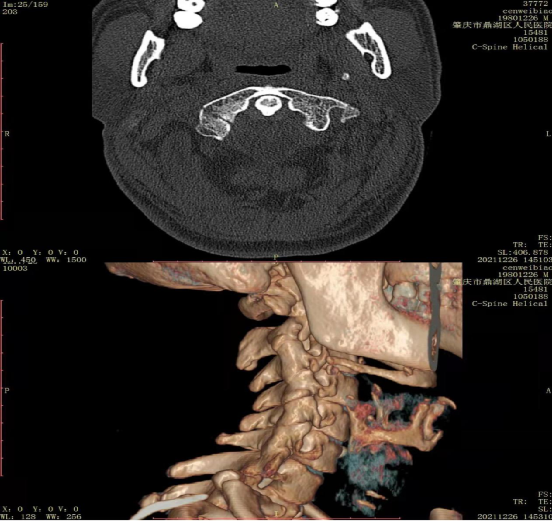

2021年12月21日,我院骨科收治了一位41岁的男性病人,因车祸致伤颈部入院,颈椎CT提示:寰椎右侧块骨折,无明显移位。入院后黎虞明主任仔细给病人做了体格检查,并认真阅读颈椎CT片,结合患者实际情况,认为适合使用Halo架外固定技术。在排除禁忌症后,黎虞明主任带领骨科团队顺利给病人实施了寰椎骨折Halo架外固定技术。固定后患者感觉良好,颈部疼痛感明显缓解,无相关并发症,生活能自理,每天定时检查外固定架的稳定性与效果,根据情况适当调整,并做好针孔的护理,预防针孔感染。

(颈椎三维CT检查)